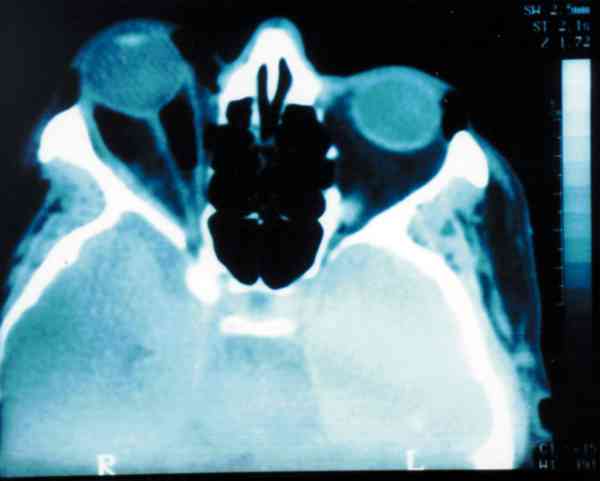

Figura 1

TOMOGRAFÍA COMPUTADORIZADA: FRACTURAS DE LA PARED INFEROLATERAL Y DEL SUELO DE LA ÓRBITA DERECHA. EXISTE UN IMPORTANTE EXOFTALMOS COMO CONSECUENCIA DEL HEMATOMA Y ENFISEMA INTRAORBITARIOS.